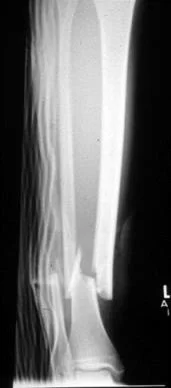

Low Energy vs. High Energy

| Low Energy | High Energy |

![]() | ![]() |